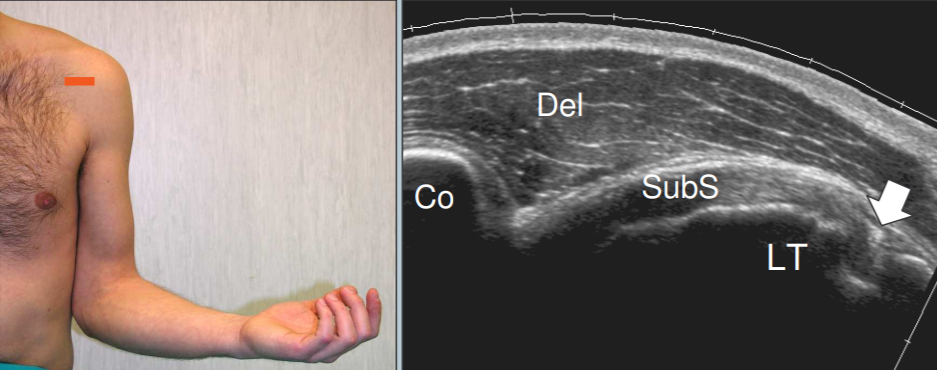

Sub-scapulaire

- Rotation externe de l’épaule, plaquée au corps

- S’insère sur le tubercule mineur

- Quelques fibres maintiennent le long biceps

- Identifier le processus coracoide

- Coupe axiale

- Coupe longitudinale: on voit bien les espaces hypoechogènes entre les faisceaux du tendon

Coupe longitudinale